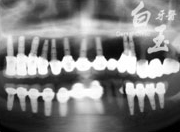

患者全口 X 光

治療前